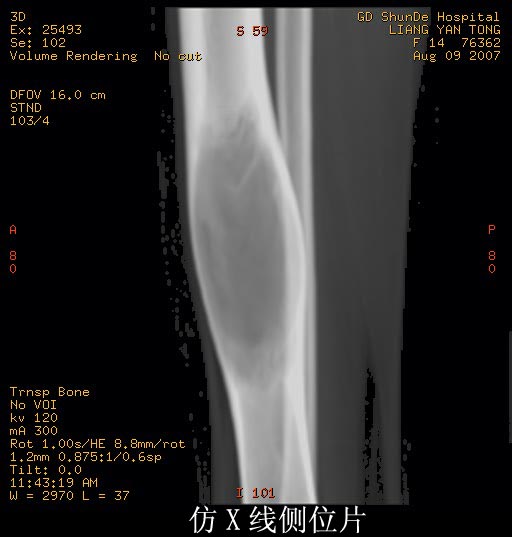

女性,14岁。自觉右胫骨下段前缘隆起。x线示:右胫骨干骨膨隆,骨皮质压迫性变薄。

支持:骨纤维异常增殖症可能。诊断依据有:1病灶呈囊状改变位于管状骨,边硬化不明显,内缘稍粗糙,囊内见条骨纹和斑点状致密影。2磨玻璃样改变,髓腔膨胀呈磨玻璃样密度。3丝瓜筋改变国缘锐利如虫蚀样,类似溶骨性转移的骨破坏。

考虑骨纤维异常增殖症。因为骨干呈囊状膨胀改变,骨皮质变薄,囊内散在条状骨纹。其内有斑点状致密影。为本病征像之一。

支持骨纤维异常增殖症。特点;膨胀性改变,呈毛玻璃样密度,其内有条点状影,没有硬化缘

没有死骨,没有骨膜反应,软组织没有肿块形成。

胫骨中段皮质内环绕并突入髓腔膨胀性生长的软组织密度病灶,内缘粗糙,外缘光滑无中断,病灶内可见小点状钙化.未见骨膜反应及瘤骨;软组织显示如常,未见肿块及异常密度.

考虑:胫骨中段良性肿瘤或肿瘤样病变,骨纤可能大.

右胫骨中段囊性、膨胀性改变,病变呈中心性,沿骨的纵轴生长,病变区骨皮质明显变薄,骨包壳完整,无中断,病变边缘无明显硬化,未见明显骨膜反应,周围软组织无肿胀。首先肯定的是骨良性病变(良性骨肿瘤或肿瘤样病变。有以下几种可能: